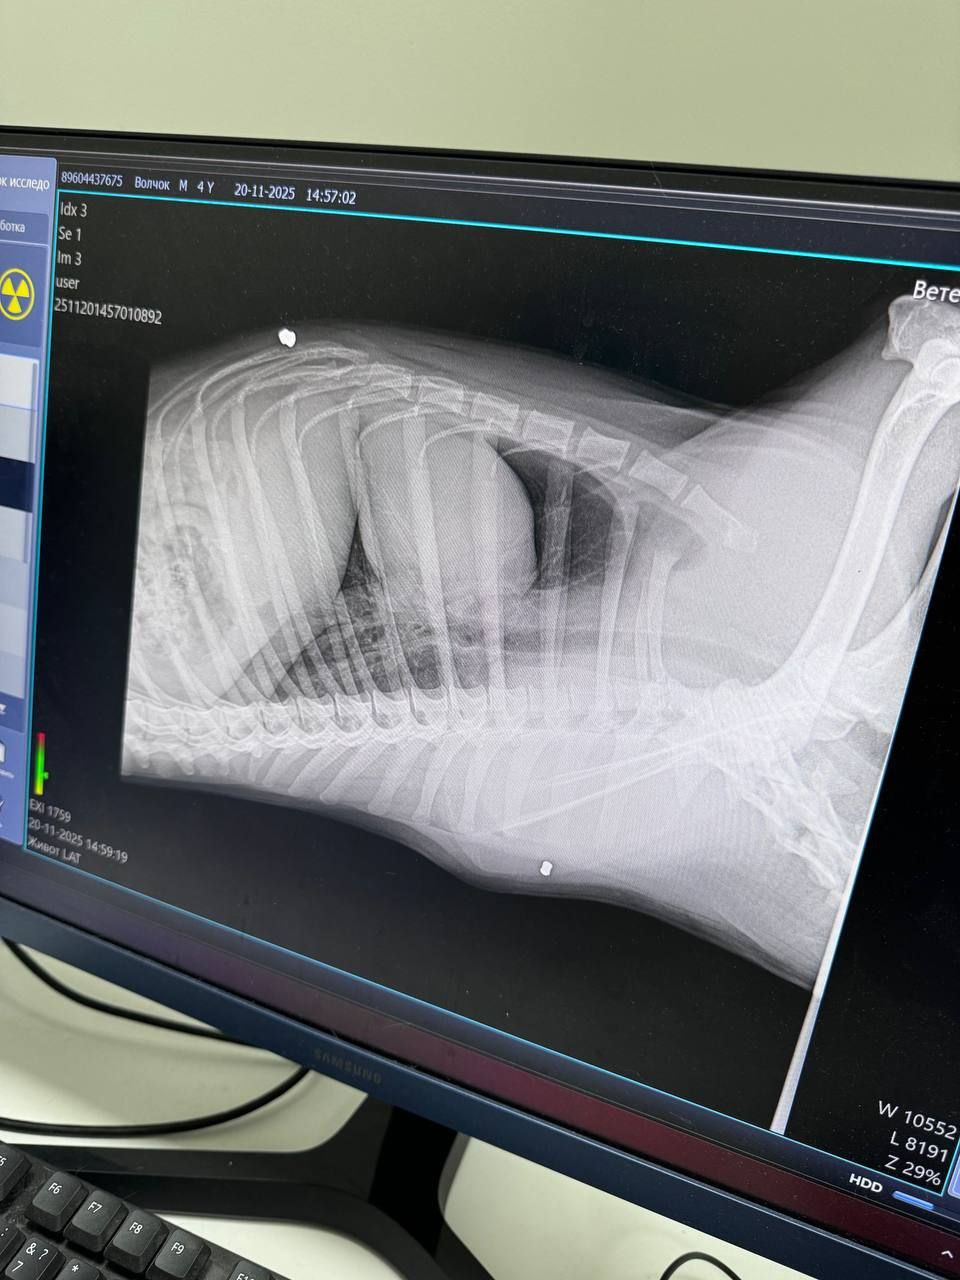

Собака была в критическом состоянии. Волонтёры доставили его в клинику, а позже - в стационар в Батайске, где обследование выявило шокирующую деталь: в теле животного нашли две пули.

- Трудно представить, что кто то способен на столь бесчеловечное обращение с живым существом! Пострадавшего пса немедленно доставили в ветеринарную клинику. Врач выявил ужасающие травмы: пробитый череп; критическое переохлаждение; множественные следы насилия. Шансы на спасение казались ничтожными! Однако, благодаря неравнодушию горожан, на следующий день собаку в критическом состоянии удалось отвезти в стационар в город Батайск. Во время детального обследования, в теле животного были обнаружены две пули! Специалисты пришли к выводу: пёс подвергался издевательствам не один день!